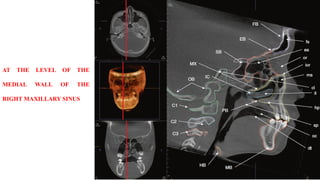

MEDIAL WALL OF THE

RIGHT MAXILLARY SINUS

AT THE LEVEL OF

THE MEDIAL WALL

OF THE RIGHT

MAXILLARY SINUS

AT THE LEVELOF THE MEDIAL WALL OF THE RIGHT MAXILLARY SINUS